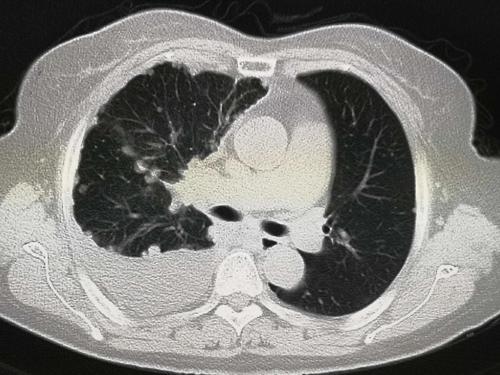

家人劝她赶紧到医院就诊,我们为她进行了肺部体格检查,右侧胸部叩诊呈浊音,听诊右肺呼吸音很低很低。初步判断,右侧存在胸腔积液。为了进一步确诊,我让她做了肺CT检查。

肺ct的结果提示右侧胸腔积液,但是肺内并没有明确的占位性病变。

右侧胸腔积液